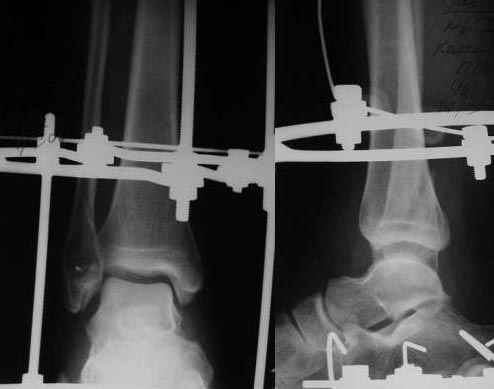

Больная, 45 лет. Открытый переломо-вывих левой стопы. При поступлении выполнена ПХО раны, скелетное вытяжение на шине Белера. Через неделю наложен АВФ, устранен вывих стопы. Это первый мой опыт лечения таких переломов в аппарате Илизарова. Интересуют вопросы:

1. Уменьшать ли высоту суставной щели голено-стопного сустава? Перестарался я, добиваясь сопоставления дистального отломка малоберцовой кости по длине. Трофических и неврологических расстройств нет.

2. Схема компоновки аппарата (на мой взгляд) не дает больной возможность опираться на ногу. Передвигается с опорой на костыли и здоровую конечность. Когда дать нагрузку? Больная категорически отказалась от проведения спиц с напайкой в условиях местной анестезии. Хотел провести спицу в репонирующем кольце для стабилизации.

3. Добиваться ли плотного сопоставления малоберцовых отломков? Если да, то как? Виден диастаз, что может, вероятно, говорить о неустраненной наружной ротации стопы.